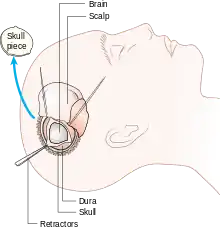

A craniotomy is a surgical operation in which a bone flap is temporarily removed from the skull to access the brain. Craniotomies are often critical operations, performed on patients who are suffering from brain lesions, such as tumors, blood clots, removal of foreign bodies such as bullets, or traumatic brain injury (TBI), and can also allow doctors to surgically implant devices, such as deep brain stimulators for the treatment of Parkinson's disease, epilepsy, and cerebellar tremor. The procedure is also used in epilepsy surgery to remove the parts of the brain that are causing epilepsy.

Craniotomy is distinguished from craniectomy (in which the skull flap is not immediately replaced, allowing the brain to swell, thus reducing intracranial pressure) and from trepanation, the creation of a burr hole through the cranium in to the dura mater.

Human craniotomy is usually performed under general anesthesia but can be also done with the patient awake using a local anaesthetic; the procedure, typically, does not involve significant discomfort for the patient. In general, a craniotomy will be preceded by an MRI scan which provides an image of the brain that the surgeon uses to plan the precise location for bone removal and the appropriate angle of access to the relevant brain areas. The amount of skull that needs to be removed depends on the type of surgery being performed. The bone flap is mostly removed with the help of a cranial drill and a craniotome, then replaced using titanium plates and screws or another form of fixation (wire, suture, etc.) after completion of the surgical procedure. In the event the host bone does not accept its replacement, an artificial piece of skull, often made of PEEK, is substituted. (The PEEK appliance is routinely modeled by a CNC machine capable of accepting a high resolution MRI computer file in order to provide a very close fit, in an effort to minimize fitment issues, and therefore minimizing the duration of the cranial surgery.)